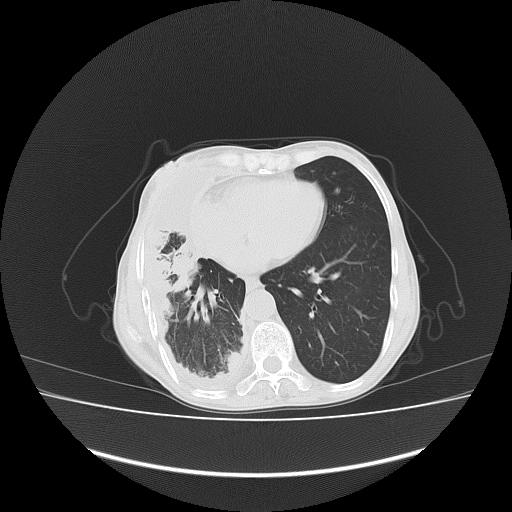

可见多发肺内病灶,且胸膜病灶较多有圆球状而非丘状,多考虑胸膜转移瘤伴胸腔积液,右侧胸廓缩小固定,且部分病灶呈丘状,尚不除外恶性胸膜间皮瘤伴肺内转移

恶性胸膜间皮瘤伴肺内转移可能性大;或胸膜、肺内均为转移瘤,左肺下叶亦见多发小结节影。

右侧胸廓塌陷,右侧胸膜广泛增厚并见多发胸膜结节,右侧少量胸腔积液并包裹。

右胸腔结节均考虑来自胸膜(部分来源于叶裂),考虑胸膜间皮瘤或转移瘤.